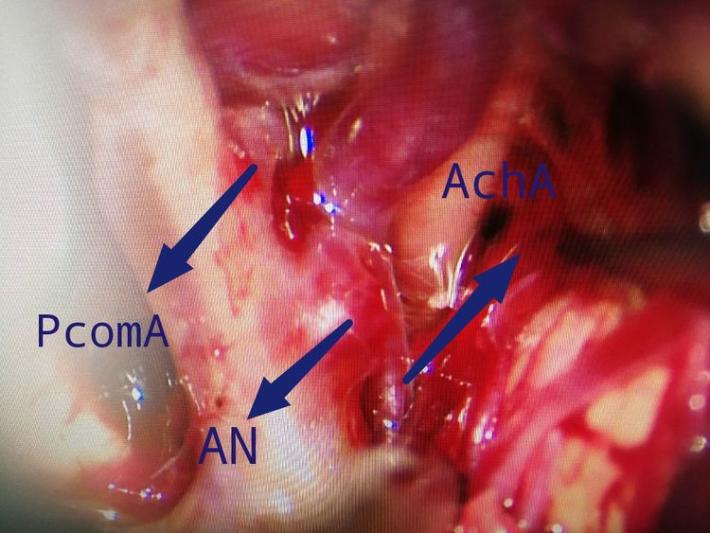

右侧翼点入路,解剖脑池系统,见前交通动脉瘤向右前伸入右侧视神经下方。予以夹闭。

显露诸血管正常。